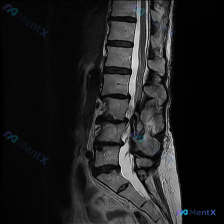

整理到一份腰椎MRI T2序列矢状位的影像学分析资料,先放影像上的客观发现,大家先从读片角度聊聊: 主要影像表现 1. 椎间盘:L2/3、L3/4、L4/5、L5/S1 T2信号明显减低(“黑盘”),伴椎间隙不同程度变窄;L4/5、L5/S1可见椎间盘向后突出,压迫硬膜囊前缘,L4/5更明显。 2....